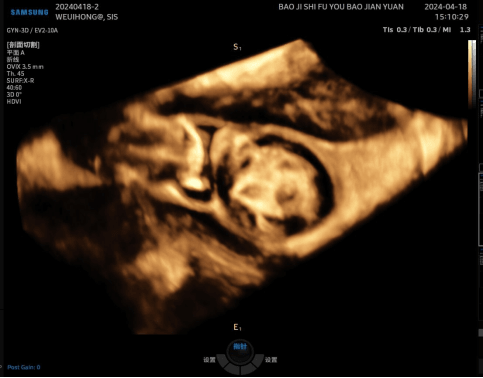

病例再现 / 01

二维超声显示肌瘤大部分位于肌壁间而不是宫腔内

宫腔水造影+三维超声显示肌瘤大部分凸向宫腔,仅有少部分位于肌壁间,二维超声不易观察到的宫腔粘连清晰可见。